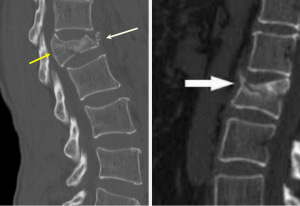

Диагностика перелома позвонка основана на нескольких моментах. Во-первых, проводится сбор анамнеза. Врач задает пациенту определенные вопросы, которые помогают определить причину травмы и ее основные симптомы. Во-вторых, врач осматривает пациента и обращает внимание на видимые симптомы. Если подозрение на компрессионный перелом становится все больше и больше, назначаются диагностические процедуры. Это третий шаг. Есть несколько исследований, которые помогают определить наличие перелома.

- Рентген. Сделанные снимки помогают точно определить, нарушена ли целостность позвонков и затронут ли L1 позвонок.

- КТ. Компьютерная томография помогает определить стабильность перелома.

- МРТ. С помощью этого метода можно рассмотреть срезы нескольких позвоночных слоев, а также диагностировать любую аномалию костей, нервов и связок.

- Сканирование. Этот метод помогает определить время, которое прошло после перелома.